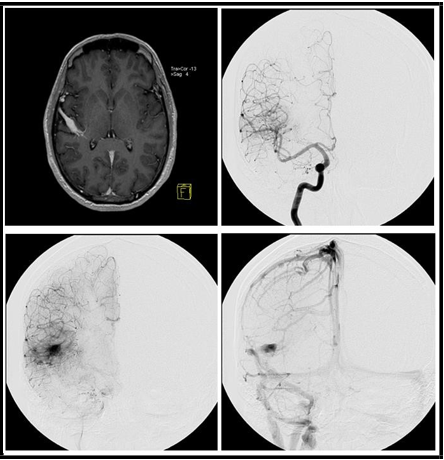

Three patients presented on this series were seen in the clinic for different reasons: One 50 years- old man was investigating recent onset of seizures, another woman aged 45 had an incidental finding during the investigation of a headache and the last one was a young woman (age 28) studied with DSA during the procedure of stereotactic radiosurgery after an episode of intracerebral hemorrhage attributed to a vascular abnormality seen on a DSA’s arterial phase. The first 2 patients were not treated for the vascular abnormality. The images seen on MR and DSA are presented in Figures 1 to 3.

Figure 2: (A) MR showing an enlarged vein with the classic pattern developmental venous anomaly (caput medusa). Lateral view sequence (B, C and D) of digital subtraction angiography demonstrating the presence of a large early draining vein, with the classical aspect of venous angioma.

Figure 3: (A) MR showing an enlarged vein with the classic pattern developmental venous anomaly (caput medusa). Frontal view sequence (B, C and D) of digital subtraction angiography demonstrating the presence of a large early draining vein, with the classical aspect of venous angioma.